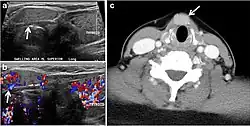

Fig. 8. A 48-year-old male patient post total thyroidectomy with PTC recurrence. a Transverse greyscale ultrasound of the neck demonstrates a left thyroid bed heterogeneous, predominantly hypoechoic irregular lesion with calcifications (white arrow). b A spot image of iodine 123 total body scan of the neck demonstrate a focus of abnormal radiotracer uptake at the left thyroid bed (Black arrows) between the annotated markers. c Enhanced axial CT scan of the neck demonstrates an enhancing large left thyroid bed mass (white arrow) with no calcifications. The lesion exerts a mass effect on the oesophagus (black arrow) and is inseparable from the trachea.[1] -

Fig. 9. A 58-year-old male patient with persistence PTC at thyroid bed with hypervascular nodal metastasis. a–c Transverse greyscale and colour Doppler neck ultrasound demonstrate hypoehoic soft tissue in the left thyroid bed (white arrow in a). There are a heterogeneous enlarged lymph nodes at level 2 and 3 with markedly increased vascularity (white arrow in b and c). d–f Enhanced axial CT images of the neck demonstrate a 2.7 × 1.4 cm hypodense soft tissue lesion anterior to the left carotid sheath (white arrow). There are left-sided enhancing abnormal and enlarged lymph nodes at cervical level 2 and 3 (black arrows).[1]